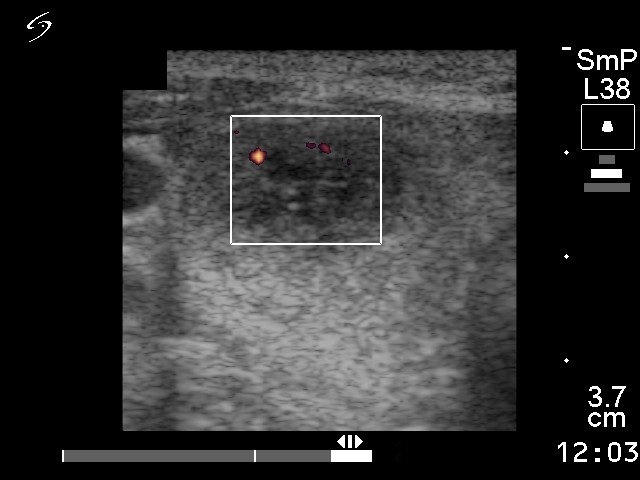

Ultrasonography disclosed a nodule with hypoechogenic, hyperechogenic and cystic parts in the right thyroid. The nodule presented a type 3 vascular pattern.